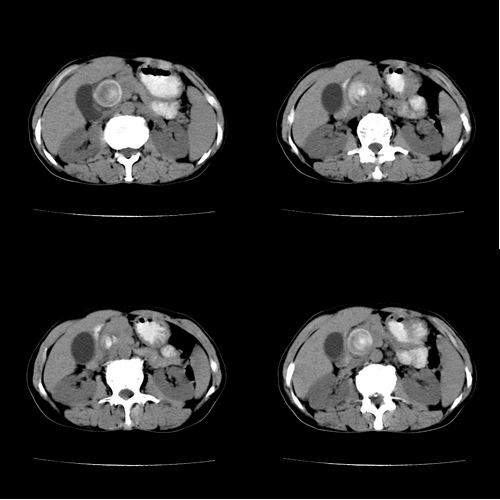

患者 女 60岁,曾多年胆结石及胆管结石,今行ct复查,非常经典.现上传,请讨论.

典型的胆总管铸型结石。

胆总管内多层同心圆样结石,确属精典,谢谢卜一老师!

同心圆样改变.典型!这样的石子值多少钱?

蛔虫性结石